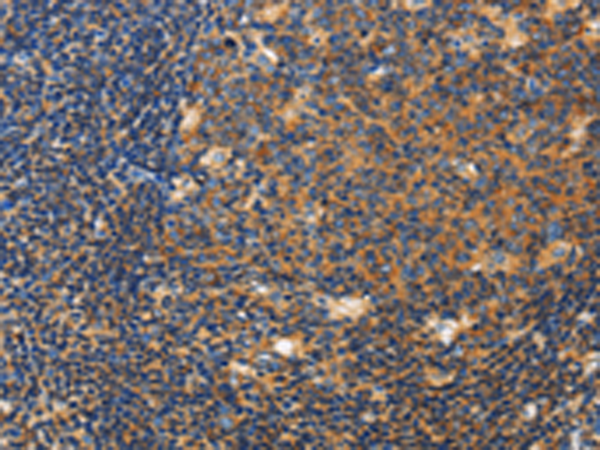

分类: 科研抗体货号: P08004别名: mATG9; APG9L1; MGD3208应用: WB,IHC反应种属: Human, Rat